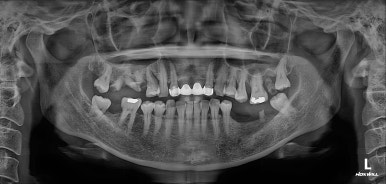

정면에서 보았을 땐, 기존에 제작되어있던 PFM 브릿지가 시간이 지나 그 경계가 조금 보이는 것 말곤 특별히 문제는 없어보였습니다. 아마도 앞니에 큰 문제가 없었기에 내원이 조금 늦어지신 것이 아닌가 싶었어요.

어금니의 상황은 조금 달랐는데요,

오른쪽 위 어금니가 충치와 마모가 심해 뿌리만 남아있는 듯한 모습을 보여주었고,

왼쪽 아래 어금니는 발치되어있는 상황이었습니다.

그리고 무엇보다, 전체 임플란트를 함에 있어 가장 고려대상이 되는 '교합평면'에 어긋나도록 자기 치아를 이탈한 치아들이 많았습니다.

내원했을 당시 처음과 비교해보면, 노란선으로 표시된 상악동 뼈이식술 라인을 관찰하실 수 있을겁니다.

그렇게해서 최종완료 후 치과용 파노라마 사진입니다!

치과치료에 대해 잘 모르시는 분이라 할지라도 보고 있으면, 치료가 조화롭게 잘 끝났구나.. 라고 아실 수 있으리라 생각합니다.

제가 제일 좋아하는 치과용 파노라마 비교 사진입니다.